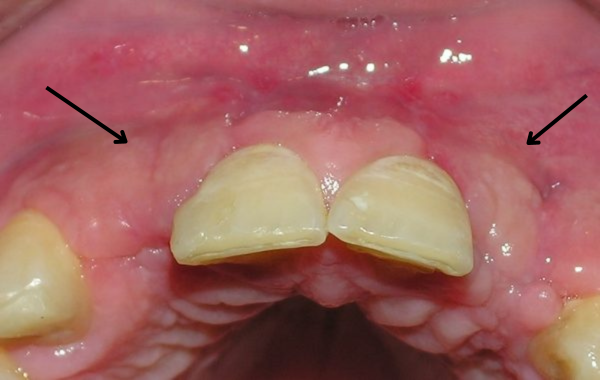

Paciente con ausencia congénita de laterales. Nótese la gran depresión del hueso

Aquí observamos el aumento de hueso debido al injerto de bloque de mentón